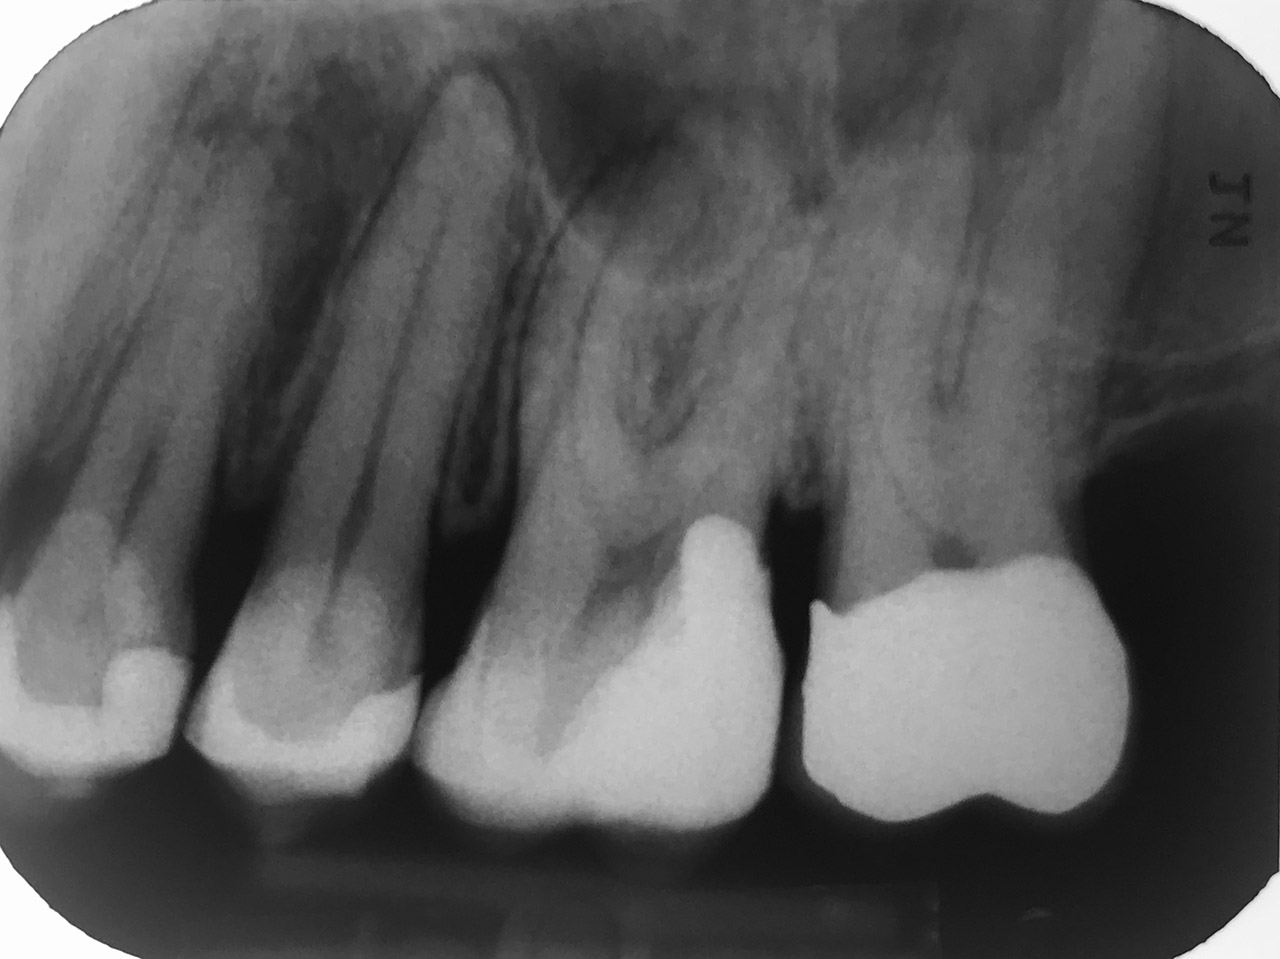

Wurzelbehandlung/Endodontie:

Massiver Paro-/Endodefekt bei den Zähnen 38&37. Extraktion von 38 (Weisheitszahn) und Wurzelbehandlung von 37 (4 Kanäle). Defekt vollständig ausgeheilt.